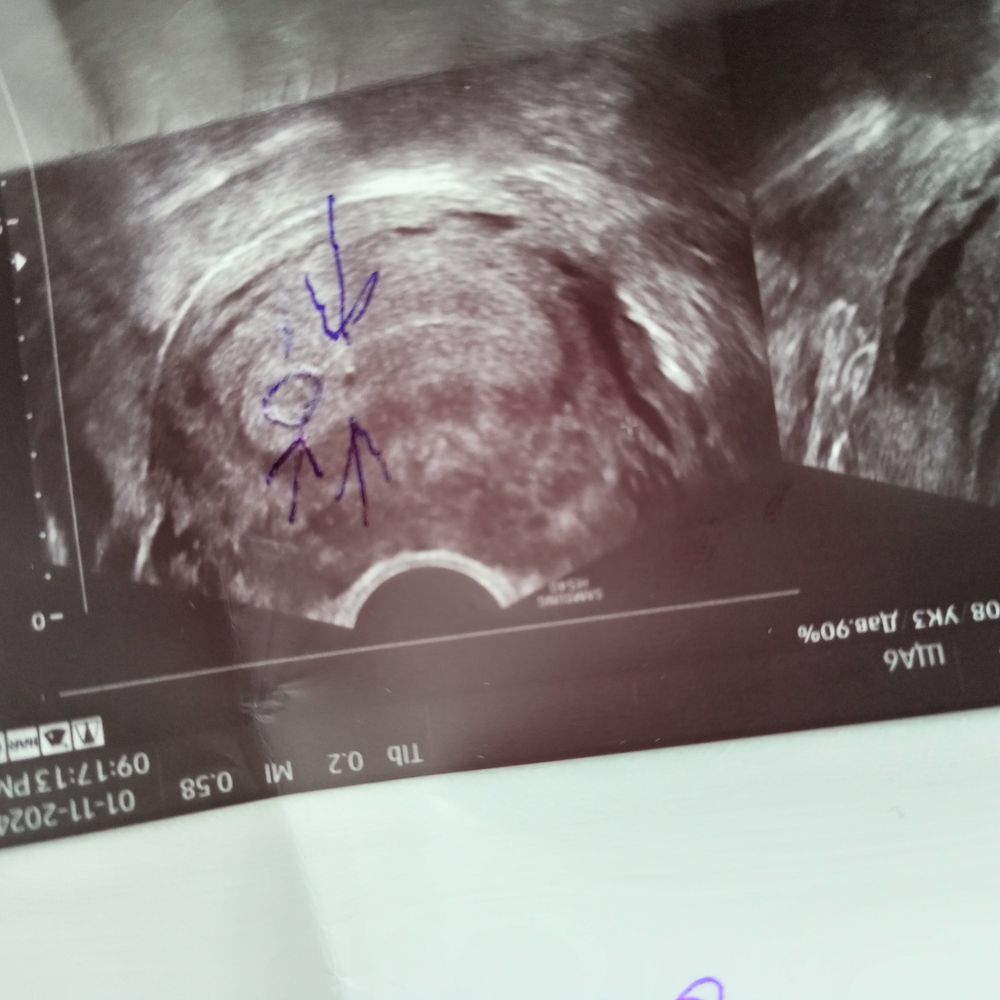

Девочки ходила на УЗИ 11 числа задержка 5 дней, плодное я. 2мм и 1.7 мм у кого такие маленькие находили и я так понимаю это 2 ребенка 🤯И какому сроку примерно соответсвуют такие размеры пя. Может кто то знает кстати тест в этот день делала показало при задержке в 5 дней 1-2 нед

Анастасия, на этой фотографии это были 2 плодных яичка смогли увидеть даже такого размера но одно потом подпосло до 16 мм и все(